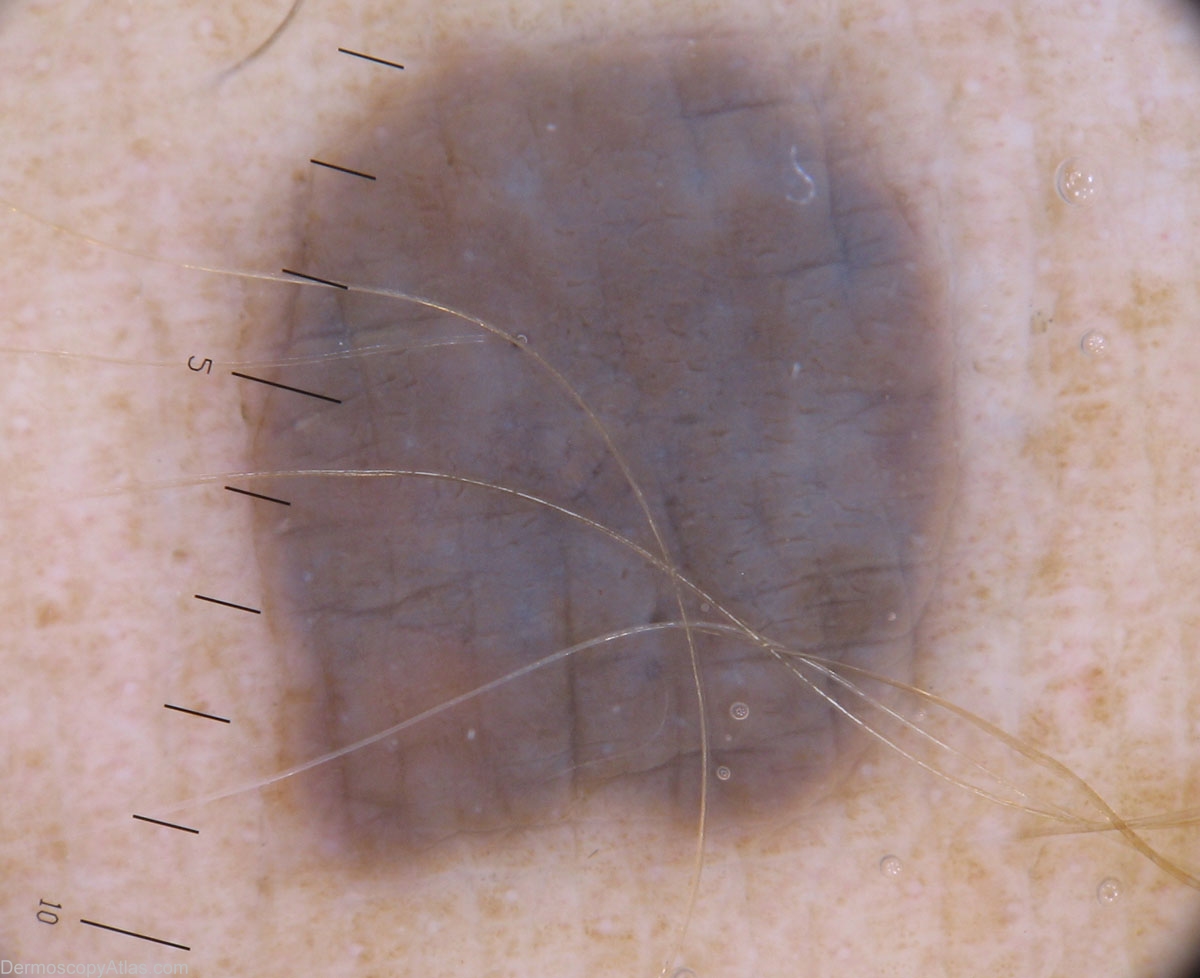

Diagnosis - Blue nevus

Diagnosis: Blue nevus